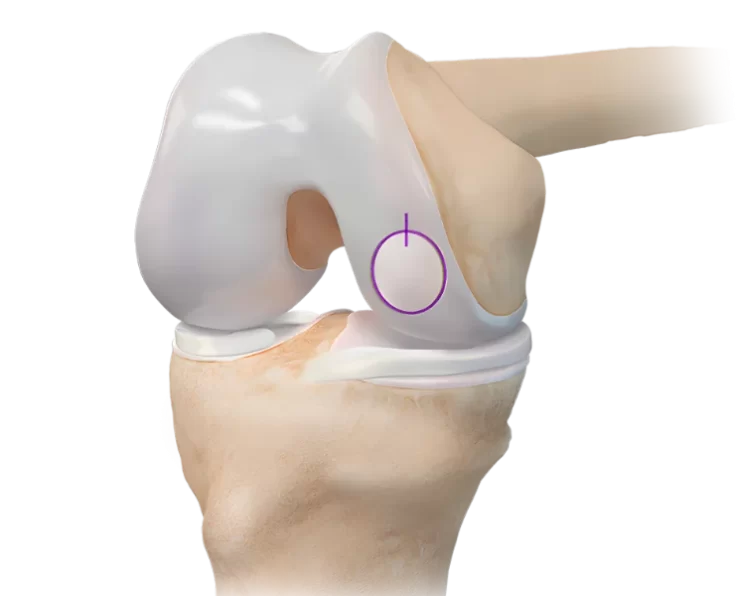

Terrible Triad in Elbow

Three injuries are combined in a horrific triad: dislocation of the elbow, radial head fracture, and coronoid fracture.

Complex Fractures in Radial Head

They account for around a third of all elbow fractures and are most common in people between the ages of 20 and 60. (with a…

Capitellum Fractures

Capitellum fractures are a discrete subset of coronal plane partial articular injuries of the distal humerus, accounting for less than 1% of all elbow fractures.

Complex Distal Humeral Fracture

A distal humerus fracture occurs when the lower end of the upper arm bone (humerus) breaks, which is one of the three bones that make…